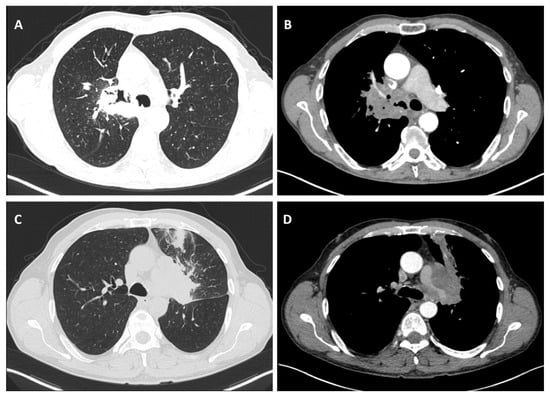

Considering the exclusion criteria previously mentioned, a total of 58 patients were analysed in this study, in which 26 cases were pathologically proven to be adenocarcinoma (Figure 1), 22 cases were shown to be squamous cell carcinoma (Figure 2), and 10 cases were shown to be small cell lung cancer (Figure 3).

Figure 1.

Axial CT of two different cases of adenocarcinoma: (A) a right peripheral mass (the maximal tumoral diameter over three centimetres) with spiculated margins, a small atelectatic area and hilar invasion is highlighted on lung window; (B) soft-tissue window that shows the same tumour as (A) with central necrosis and pleural invasion, including the main right bronchus; and (C,D) a peripheral mass with adjacent pneumonitis in the left lower lobe.

Figure 2.

Axial CT of two different cases of squamous cell carcinoma: (A,B) show a right hilar mass with cavity and air bubbles inside, with invasion of the hilar vessels and right main bronchus extending over less than 2 cm from the carina; and (C,D) show a left hilar mass with atelectasis, necrosis, septal thickening, and important invasion of the pulmonary trunk and left pulmonary artery.